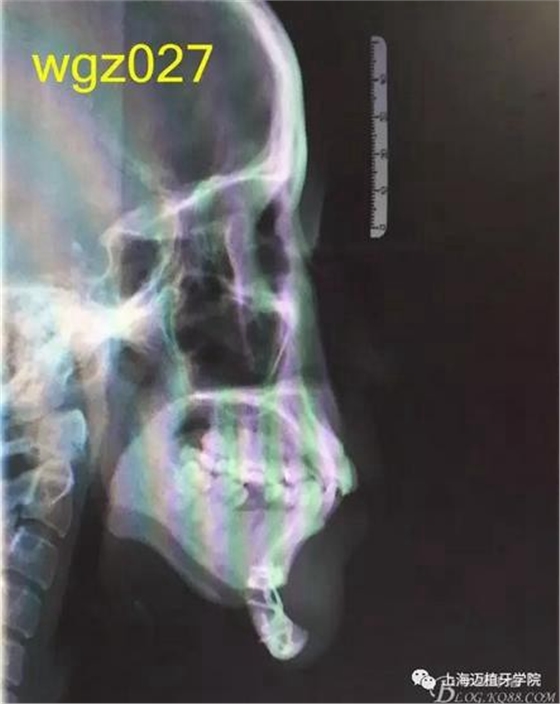

根據(jù)以下上傳的圖片及X線影像資料,你認為她的牙齒存在什么問題?應(yīng)該如何進行矯治設(shè)計?

上海萬眾醫(yī)院正畸科進修醫(yī)生魏倩倩作業(yè)。 某女,25歲。 主訴:頦部術(shù)后自覺牙齒不齊,牙齒凸要求矯正。 既往史:曾有顳下頜關(guān)節(jié)疼痛史,于外院診斷為關(guān)節(jié)不可復(fù)性前移位伴髁突不對稱,行關(guān)節(jié)盤復(fù)位術(shù)。約3個月前在外院行頦成形術(shù),現(xiàn)因牙齒不齊,牙齒凸前來就診。 口外檢查:正面觀,長面型,左右基本對稱,面下1/3過長,頦部明顯水腫,質(zhì)硬; 側(cè)面觀,面型稍凸。 顳合關(guān)節(jié)檢查:無壓痛,左側(cè)彈響,兩側(cè)髁突運動基本一致。 口內(nèi)檢查:恒牙列,下頜前庭處縫合,傷口愈合良好??谇恍l(wèi)生情況一般,牙齦紅腫,LR2、LL6缺失,UR456舌傾與LR67成反合關(guān)系,UR3頰側(cè)突出移位,UR2UL2近中扭轉(zhuǎn),UL1近中外翻唇傾,UR7UL7頰傾,LR6近中傾斜升高,LR5近中傾斜,LR4頰傾移位,LR3冠舌側(cè)傾斜,LL2近中扭轉(zhuǎn)冠頰傾,LL3舌傾,LL78近中傾斜。 模型分析:上頜前牙段擁擠度9.5mm,下頜前牙段擁擠度9mm,spee左右約3mm, LL5、LL7之間間隙約為5mm。上下中線右偏約1.5mm。全牙比約為80%,前牙比62%。磨牙關(guān)系:右側(cè)近中關(guān)系,UL6與LL7遠中尖對尖。尖牙關(guān)系:右側(cè)遠中關(guān)系,左側(cè)近中關(guān)系。 行為分析:患者已于外院行頦成形術(shù),面型已改善,但患者仍覺得牙齒凸,說明患者非常重視面型問題,對美觀要求高。 頭顱側(cè)位片:面型稍凸,上唇在E線前約1.5mm,下唇在 E前約1mm 。 SNA: 85↑ SNB: 75↓ANB: 10↑ U1-L1: 113.6↓ U1-SN: 107.9 L1-M P: 88 ↓Y軸角:65.8 FH-MP: 37↑ SN -M P: 45↑ 曲面斷層片:28顆恒牙,LL6缺失,牙槽骨均位于釉牙骨質(zhì)界以下,LR6、LL7近中牙槽骨角型吸收,頦部可見成型術(shù)鈦合板。左側(cè)升支較右側(cè)粗。 關(guān)節(jié)片:左右髁突不對稱,髁狀間隙右側(cè)明顯較左側(cè)寬,右側(cè)間隙清楚,大小勻稱 ,左側(cè)欠佳。 診斷:安氏3類 骨性2類 高角 上下前牙重度擁擠 中線不齊 間隙分析:下頜 , LL5與LL7之間的有5mm間隙,下頜擁擠度為9mm,整平下頜曲線需要約3mm間隙,下頜需要約12mm間隙,減去現(xiàn)有間隙還需要7mm間隙。上頜,擁擠度為9.5mm,擁擠主要集中在前牙段。 支抗分析:患者頦部術(shù)后仍覺面型凸(主要是上頜前突),所以除了要解決擁擠度外還需要內(nèi)收前牙,所以上頜需要強支抗。患者SNB為75,下頜發(fā)育不足,高角,相對低角病例來說,下頜磨牙較易前移。下頜前牙重度擁擠的情況下主張只解除擁擠不宜內(nèi)收(該患者系下頜后縮病例)。患者ANB為10°,本屬于正頜正畸聯(lián)合治療,現(xiàn)患者已做頦部成型術(shù),患者面型得到改善,故患者現(xiàn)在主要為解決擁擠,少量內(nèi)收前牙,解決上前牙凸度。